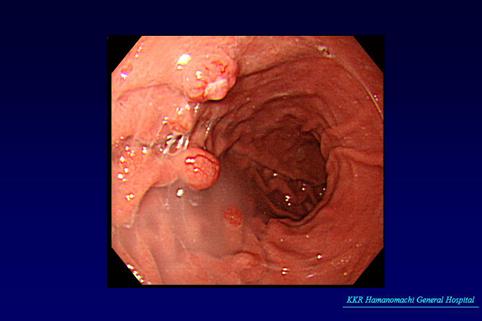

Múltiples Carcinoides Gástricos

Fukuoka Pref., KKR Hamanomachi General Hospital (KKR Hamanomachi General Hospital)

femenino

50-54

Tumor Carcinoide/

estómago(región)/mas de dos

Endoscopia

1 - 9

sm

presente(simultáneo)